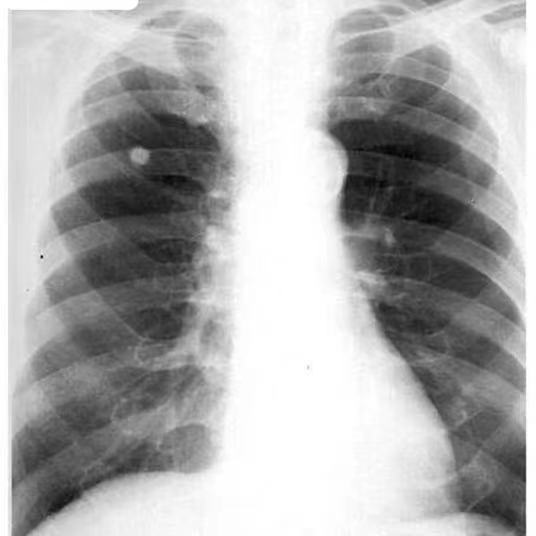

结核杆菌是能导致肺部炎症的因素之一,痊愈后可能形成钙化灶,一般表明肺结核病灶基本好转、痊愈或不存在活动性结核杆菌,不存在传染性。少部分健康人群因自身免疫力较强,感染结核分枝杆菌后不出现明显症状,免疫应答可直接将细菌消灭,达到自愈而形成钙化点,此钙化灶对机体无任何影响。

有明确肺结核病史且有规范抗结核治疗史的患者,肺钙化点属于稳定性病灶,是治愈的表现,需定期复诊胸部摄片检查,无需特殊治疗。

如果患者没有明确的肺结核病史以及结核病接触史,也没有其他不适症状,仅由体检发现肺钙化灶,患者可定期随访观察。若钙化灶形态、大小无改变,只需定期复诊检查,无需特殊治疗。